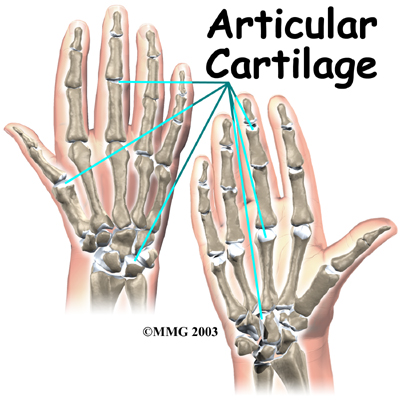

The joints of the hand, fingers, and thumb are covered on the ends with . This white, shiny material has a rubbery consistency. The function of articular cartilage is to absorb shock and provide an extremely smooth surface to facilitate motion. There is articular cartilage essentially everywhere that two bony surfaces move against one another, or articulate.